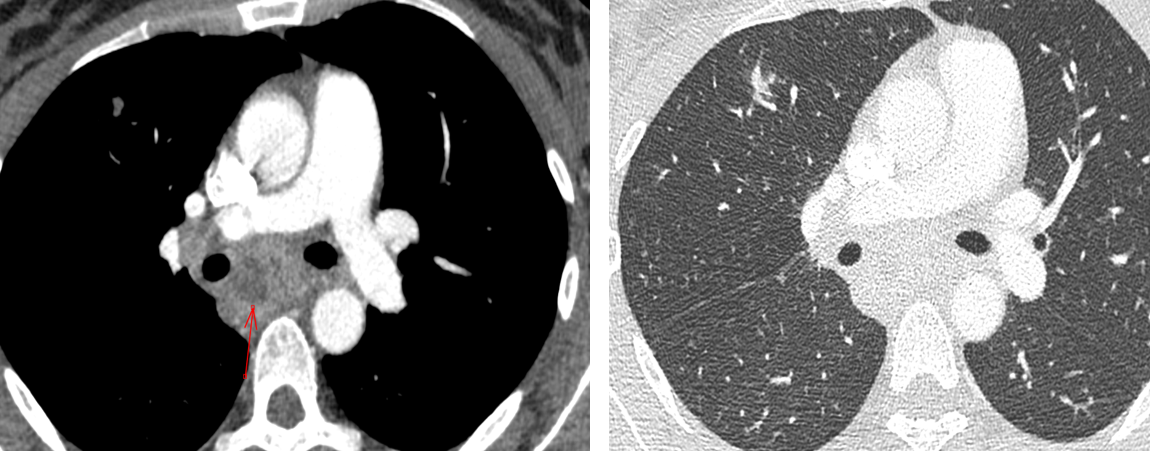

CT

- Masse solitaires avec adenopathies, confondues avec cancer ++

Lesion excavée et ADP

Confondu avec cancer, prouvée biopsie